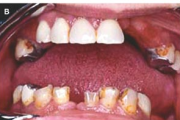

Sjögreni sündroomi võimalusele mõeldakse silmade ja suu kuivuse all kannatavatel patsientidel. Süsteemne haigus, mida iseloomustab kõigi eksokriinsete näärmete talitluse puudulikkus kroonilise põletikulise destruktsiooni tõttu. Keratokonjunktiviit Kserostoomia Polüartriit Loe edasi »